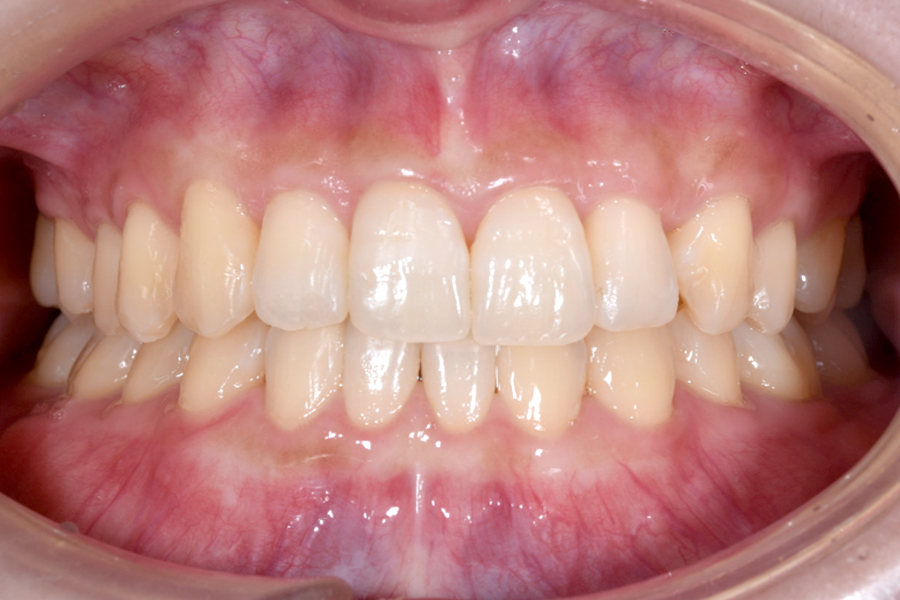

| 主訴 | 上下前歯のガタツキが気になる |

|---|---|

| 治療期間 | 1年4か月 |

| 治療費 | マウスピース矯正とホワイトニングセット 1,018,296円(税込) |

| 治療内容 | 目立ちにくいマウスピース矯正(非抜歯矯正) 歯と歯の間に隙間をつくることにより、歯列弓を広げながら治療を行いました。 また矯正用マウスピースをトレー代わりにし、ジェルを入れてホームホワイトニングを同時に行っております。 |

| 治療のリスク |

・後戻りする可能性があるのでリテーナーを最低でも矯正期間以上はつけること。 ・ホワイトニング後、一時的に痛みが出る場合があります。 ・稀にほっぺた、唇、舌などに口内炎や傷ができることがあります。 |